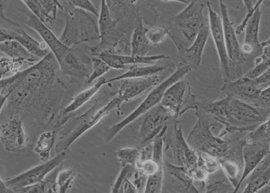

間質細胞是這個器官記憶體在的那些輔助實質細胞完成器官功能的細胞。 比如腦內的神經元細胞就是實質細胞,神經膠質細胞起支持營養神經細胞的作用,算是一種間質細胞,再如肝臟細胞是實質細胞,肝小葉間的纖維細胞就是間質細胞,起支持作用

位於曲細精管之間的組織呈疏鬆狀,稱為間質,裡面有豐富的血管淋巴管

是將人體內的營養物質供應到曲細精管處的必經之地。除此之外,裡面還有一種具有分泌雄性激素功能的細胞,叫做間質細胞。這種細胞雖小,可是功能驚人,它所分泌的雄激素分布到全身,維持男性性徵和男性性功能,同時有促使生精細胞發育成精子和促使人體的合成代謝的重要作用。